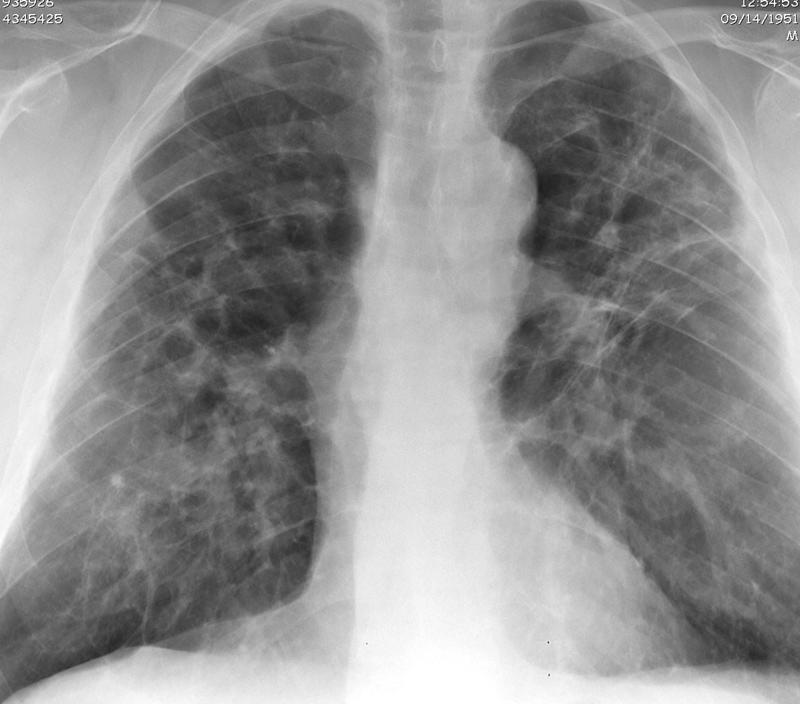

Sarcoid

Sarcoid-late Case 19 PA

Sarcoid-late

Case 19 PA